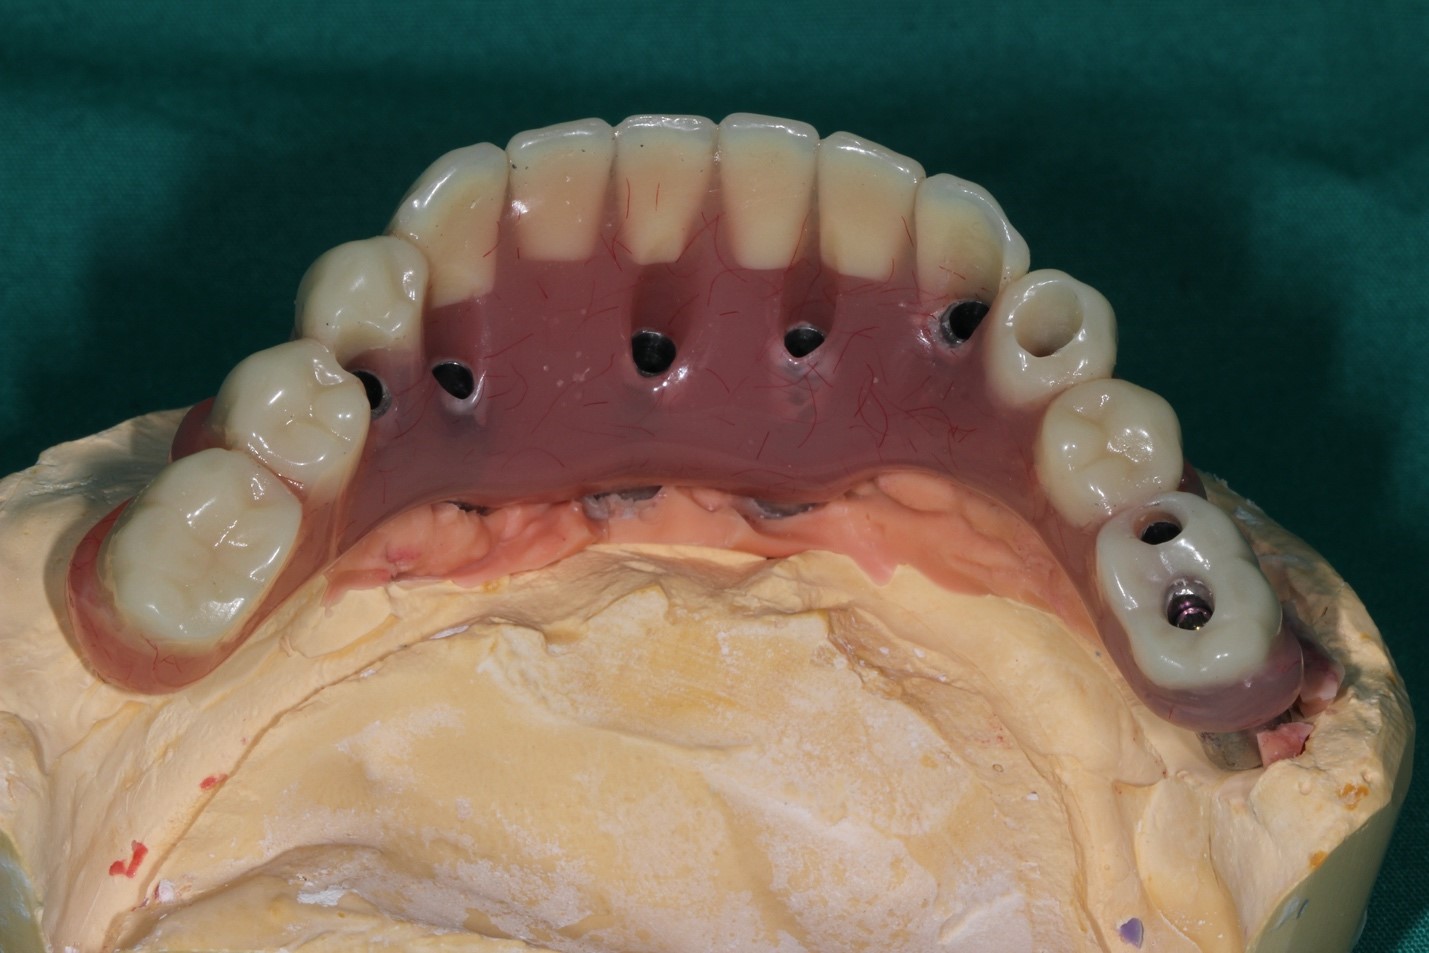

Далее импланты интегрировались и мы стали делать постоянный протез:

Далее поверх этого металла мы нарастили керамику, стало вот так:

Это контроль промывных пространств, окончательные протезы, окончательный внешний вид

На этой стадии пациент мог весело улыбаться, открывать пиво зубами (не рекомендуется, но технически мог бы), жевать стейк любой прожарки без усилий и в экстренных ситуациях перекусывать во рту металлический кабель сечением до 12 мм без особых последствий (строго не рекомендуется, даже на спор). Металлы основания конструкции — кобальт и хром. Обычно альтернатива металлокерамике — титановый каркас и цирконий, но в данной ситуации из-за геометрии такой сборки возможности её использовать почти не было, и выбрали керамику на кобальт-хроме. К титану керамика не крепится, не удерживается. Десна, естественно, не могла быть восстановлена, поэтому она фактически нарисована на керамике — это так называемая высокоэстетичная конструкция, то есть при разговоре можно и не догадаться, что зубы ненатуральные (если вы не врач).